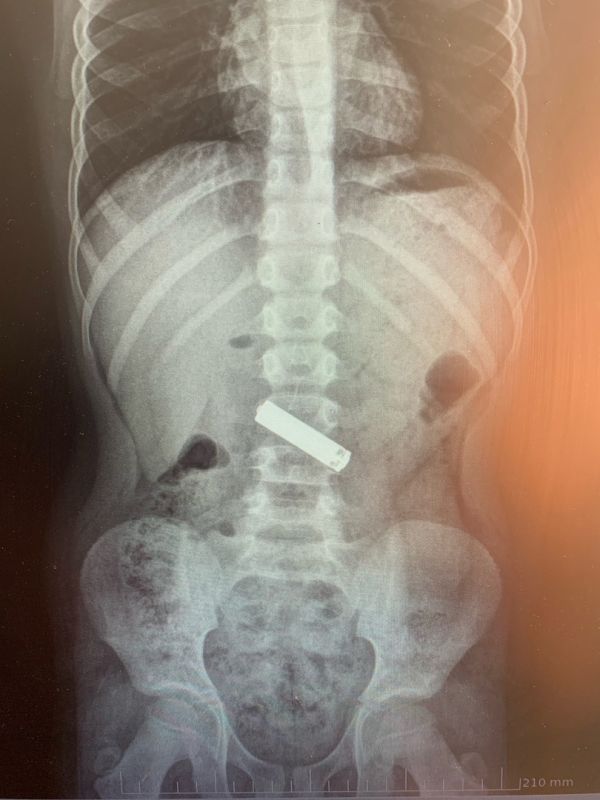

В приёмное отделение доставили 9-летнего пациента. Выяснилось, что двумя часами ранее тот проглотил «мизинчиковую» батарейку во время игры. Юного пациента осмотрели, сделали ему рентген брюшной полости.

Врачи обнаружили инородное тело и под общим обезболиванием провели эндоскопическое удаление предмета (проводится с использованием трубки с чёткой оптикой, которая позволяет видеть пораженный орган на мониторе и проводить необходимы врачу манипуляции. — Прим. «Ё!»).